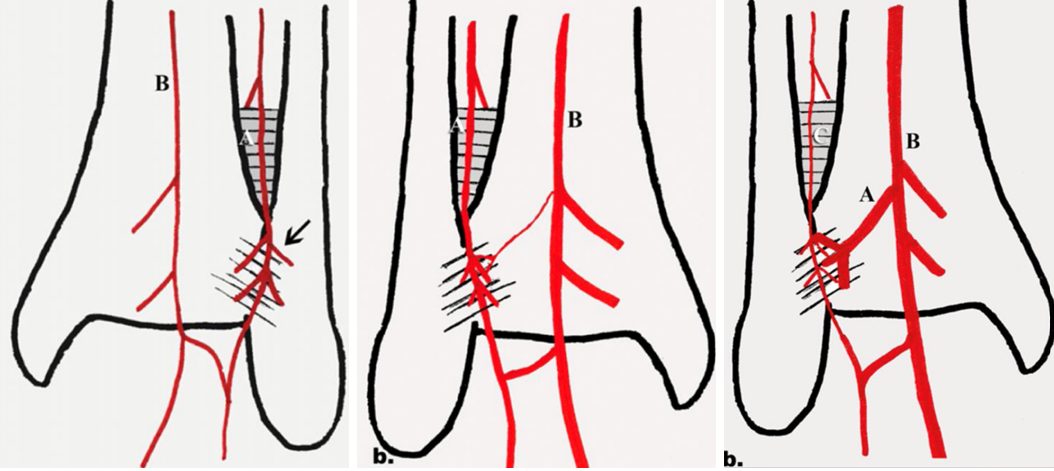

Также в области проксимальной части межберцового синдесмоза может проходить ветвь малоберцовой артерии, которая формирует анастомоз с большеберцовой артерией. В ряде случаев данная ветвь имеет большой диаметр и её повреждение при установке позиционного винта может вызывать сильное кровотечение.

Рис. 10. Варианты расположения сосудов в области межберцового синдесмоза